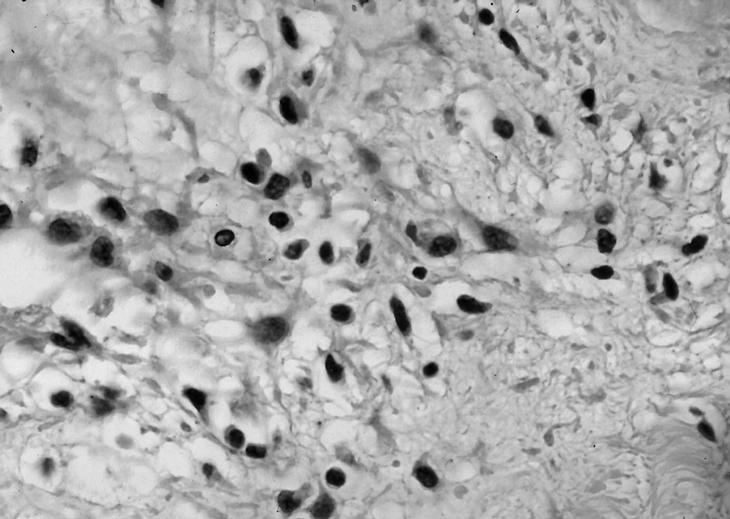

Sin embargo, a pesar de la aceptación de la teoría mecánica en el síndrome subacromial, resulta controvertida la relación directa de los factores extrínsecos descritos por Neer1-3. En la bibliografía existen trabajos que realzan la implicación de los factores intrínsecos como responsables primarios en la degeneración tendinosa (fig. 1). Codman8 y Uhthoff et al9 denominan zona crítica del músculo supraespinoso a la que se encuentra situada a 1 cm de la inserción humeral, caracterizada por su precariedad vascular.

Figura 1. Degeneración mixoide del tendón supraespioso (H-E, 400x).